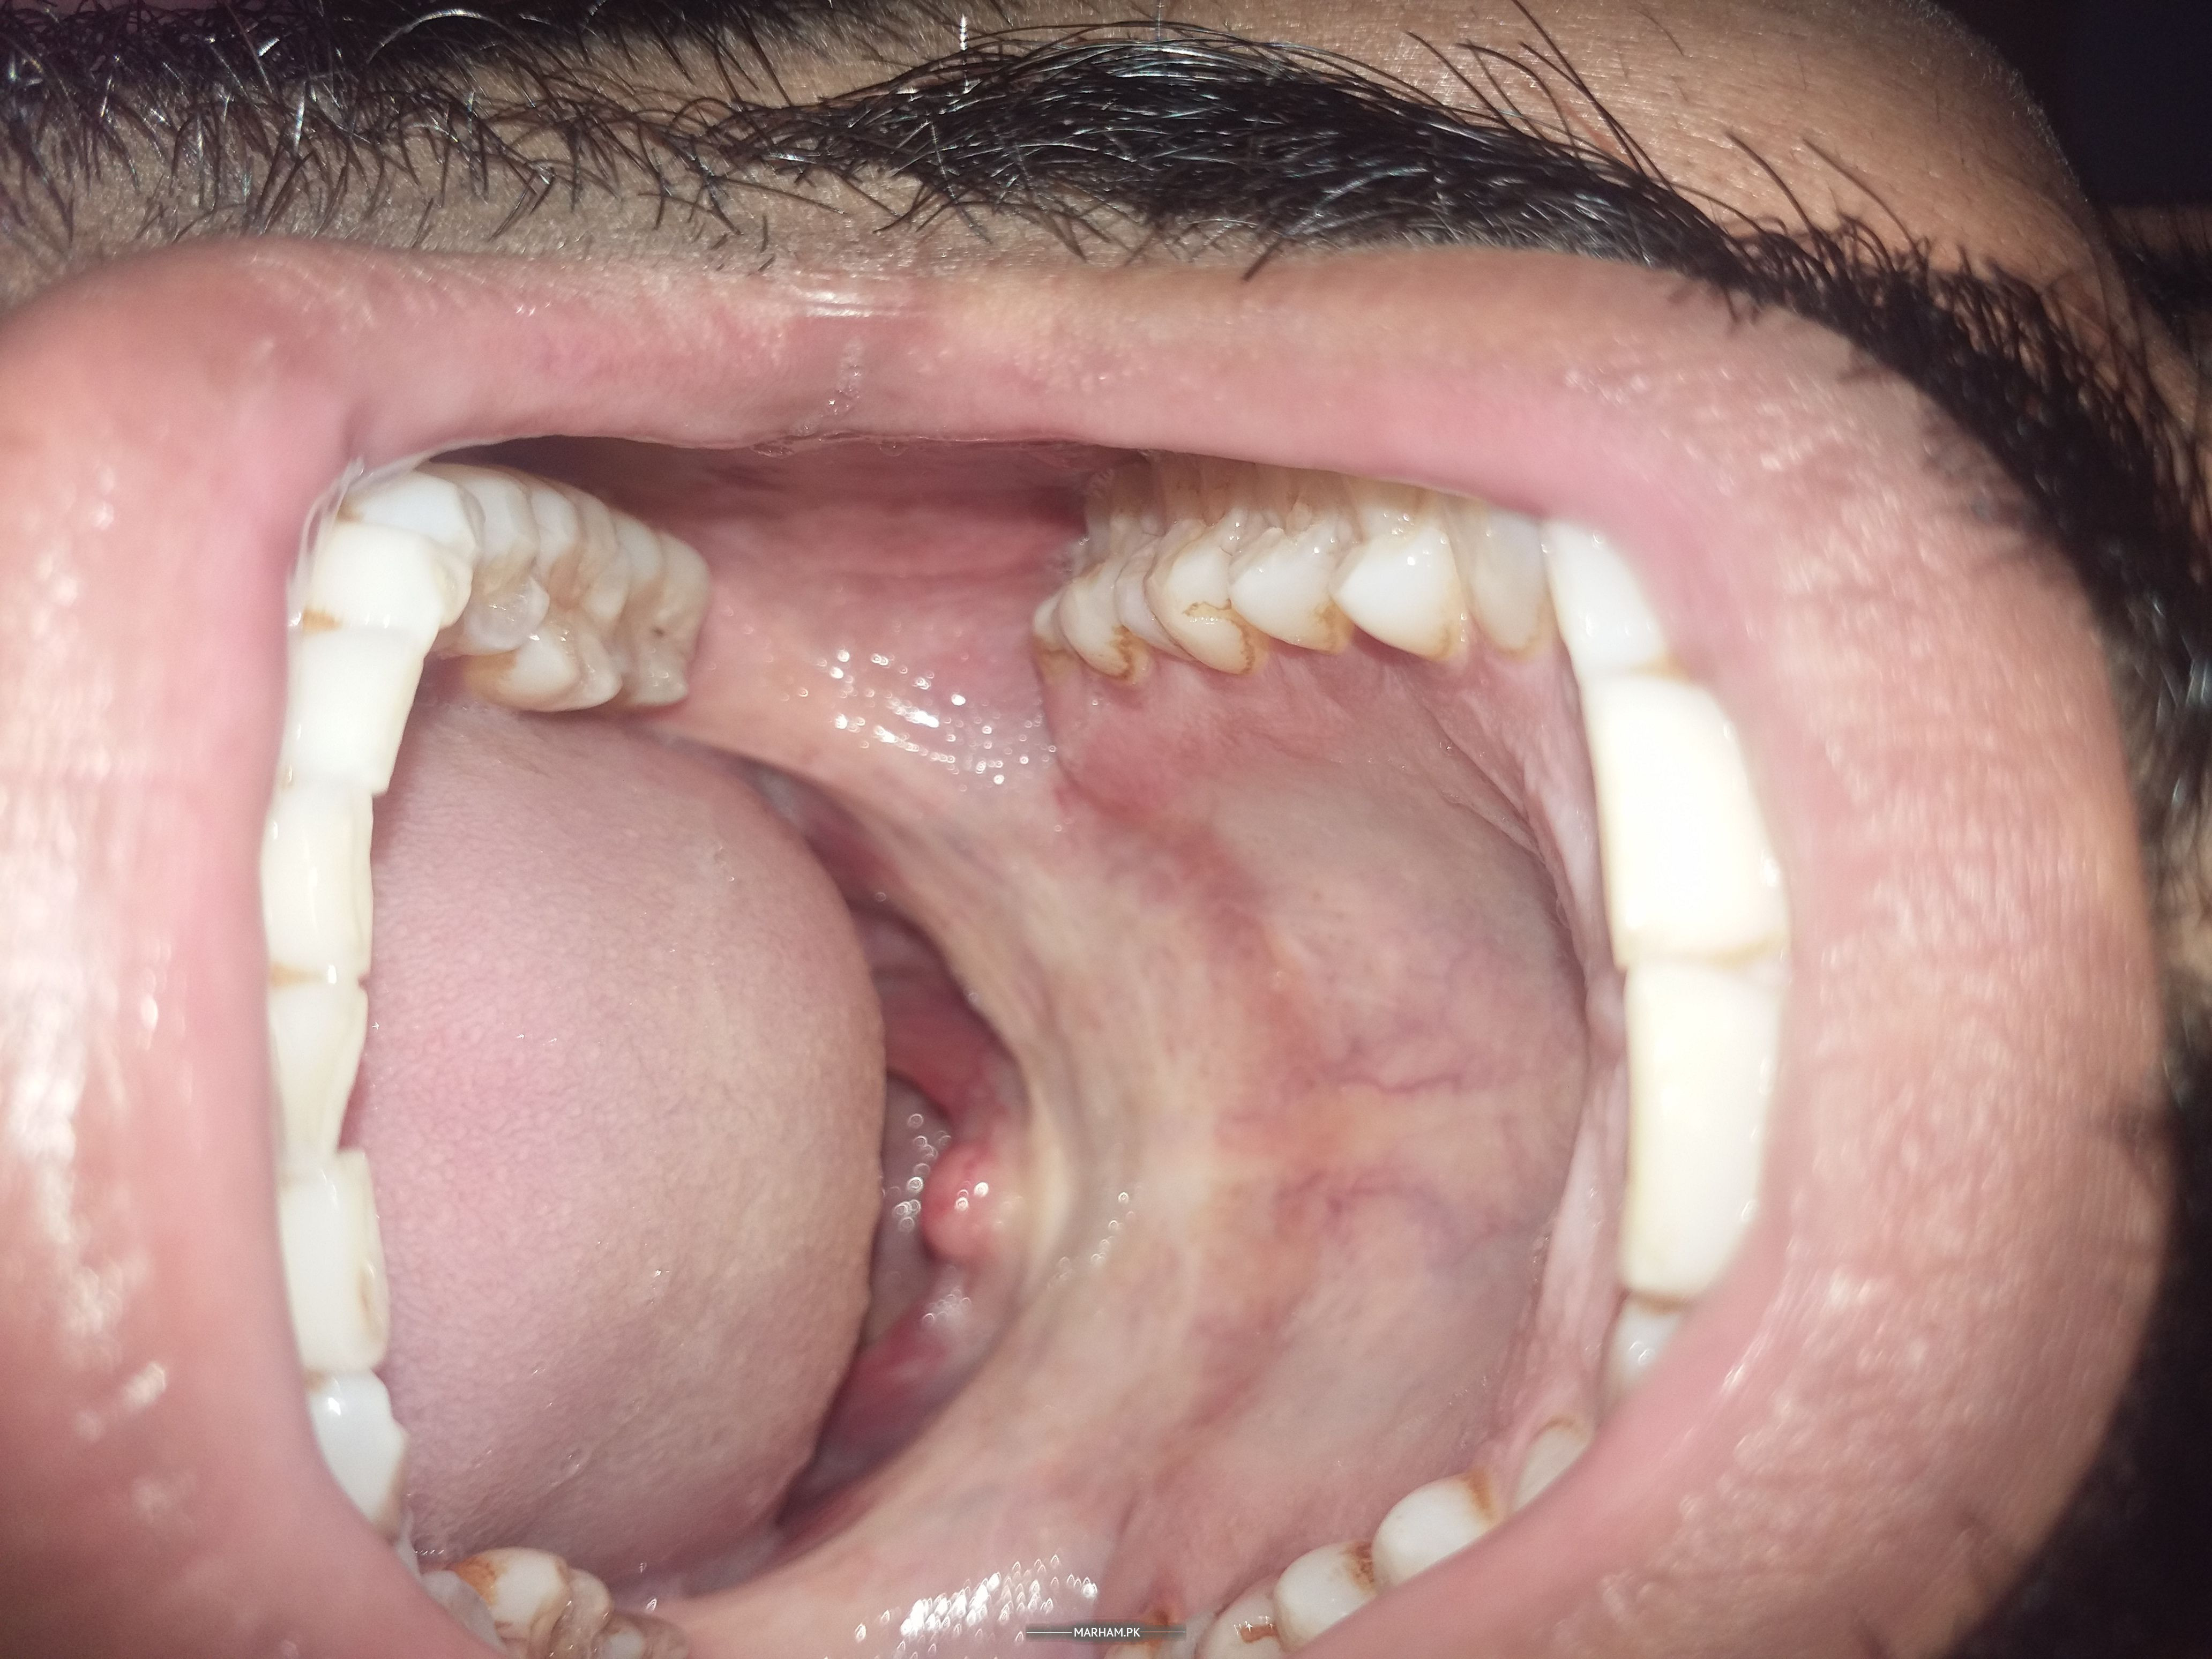

Asking for Self, Male, 26 years old, Karachi

I can put 3 fingers in my mouth. I have some zakham at my inside jaws. There is whiteness in my mouth. I visited to BDS he said i am suffering from submucous Fibrosis. Now i have stop eaten areca and betal nut. I sm taking sangobian and Vidaylin T tablet daily. After lefting these, the disease is still progressive or it may stop?. Also i want a right doctor for this disease kindly guide me where to visit in Karachi?

can u please share picture of inside of your mouth?

Pic 1